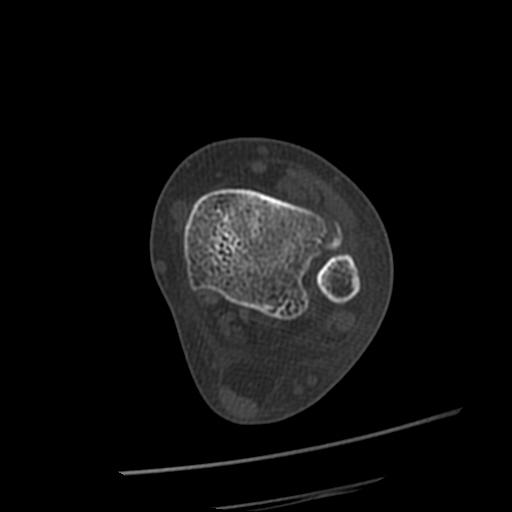

[¹ß¸ñ] distal tibiofibular ligament sprain with avulsion fracture of tibia

CT : avulsion fracture of distal tibia at distal tibiofibulat ligament insertion.